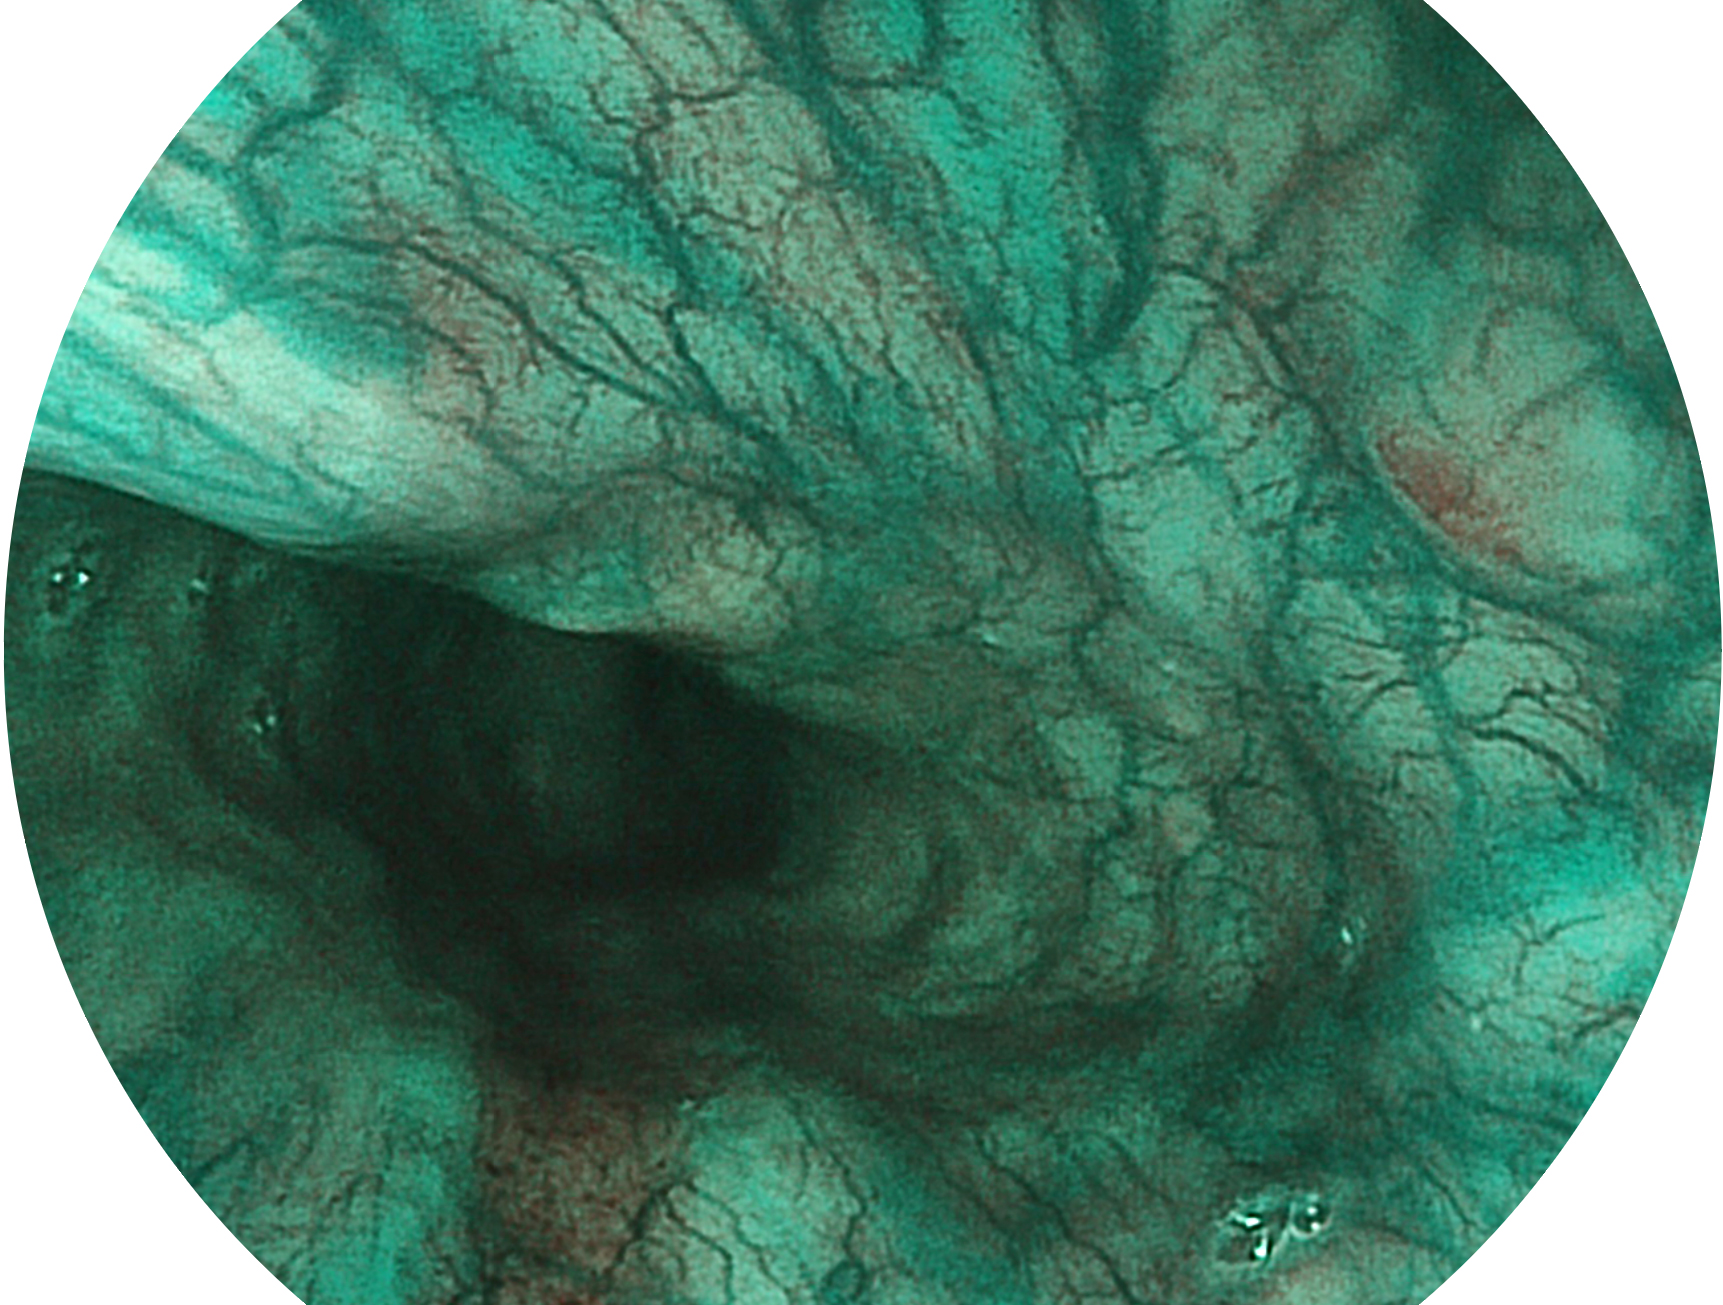

球速体育入口新开发的内镜染色技术,主要是基于多波长LED 光源的开发,VLS-55Q 四波长LED 光源是由四个不同颜色的LED光按照相应照明模式所规定的特定发光比例进行合束后形成,合束后形成的照明光的光谱由红光、绿光、蓝光及蓝紫光这四个不同的波段范围构成。具有更高光谱自由度,通过光谱比例的控制,实现了聚谱成像技术,英文全称为“Spectral Focused Imaging, SFI”,缩写为“SFI”和光电复合染色成像技术,英文全称为“Versatile Intelligent Staining Technology, VIST”,缩写为“VIST”。